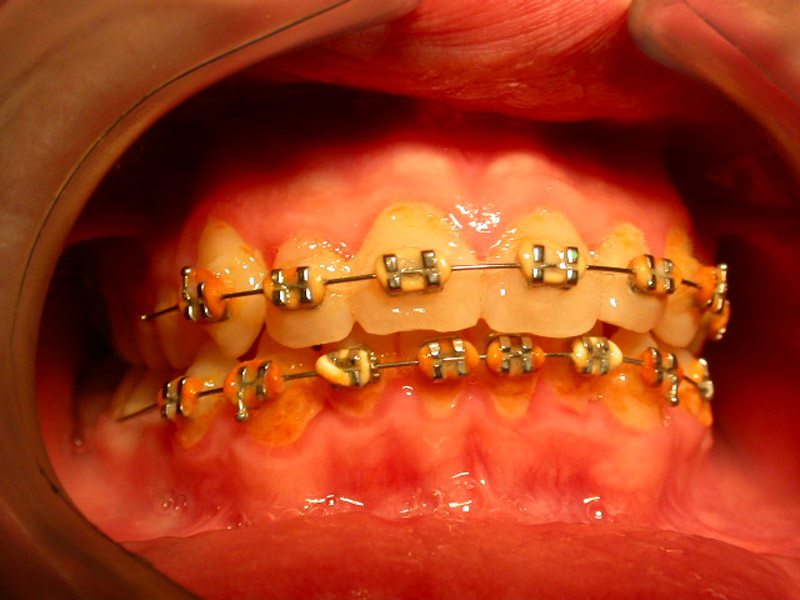

Except for the bad oral hygiene, gingivitis is related to hormonal changes during puberty or pregnancy, or the presence of orthodontic mechanisms in the mouth that make difficult to maintain good oral hygiene.